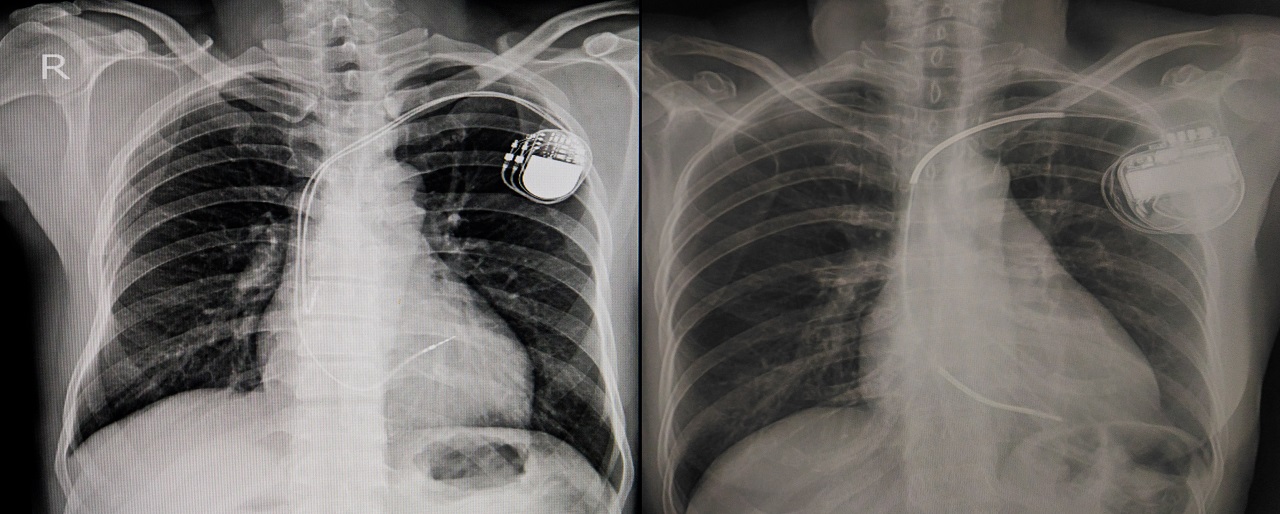

Pacemakers are inserted to help regulate electrical problems with the heart. This device is usually recommended to make sure the heart doesn’t beat at a dangerously low rate. It is usually inserted in the chest, right below your collarbone. Pacemakers can help patients with arrhythmia continue living a healthy life.

The surgery typically takes one to two hours and requires you to be awake. A sedative will be used to relax you and a local anesthetic will numb the area. Your surgeon starts with a small incision near your shoulder. A small wire will then be guided through the incision into a major vein. This major vein is usually near the collarbone. Your surgeon will then lead the wire through the vein of your heart. An X-ray machine will be used during the procedure to help the surgeon throughout the process.

With the help of the wire, your surgeon will attach the electrode to your heart. The opposite end of the wire is then attached to the pulse generator. Your new pacemaker will be located under your skin, just by your collarbone. The surgery is then closed off with the stitching of your incisions.